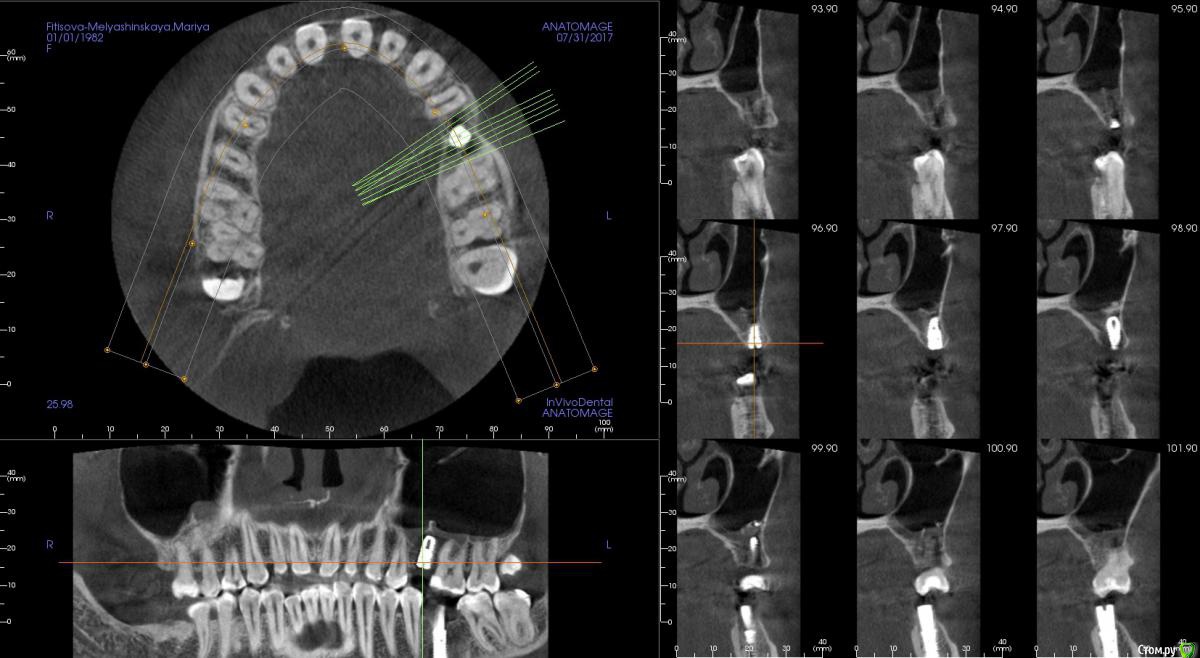

kamranchick Опубликовано 24 июля, 2017 Автор Поделиться Опубликовано 24 июля, 2017 Сработает. Комп рисует без 1,5-2 мм, так что очень даже. Апикально кость с фрезы прям в перегонку стукнуть?))) Ссылка на комментарий

kamranchick Опубликовано 31 июля, 2017 Автор Поделиться Опубликовано 31 июля, 2017 Как то вот так получилось Ссылка на комментарий

Bobon Опубликовано 31 июля, 2017 Поделиться Опубликовано 31 июля, 2017 длина 8,5? Ссылка на комментарий

kamranchick Опубликовано 31 июля, 2017 Автор Поделиться Опубликовано 31 июля, 2017 длина 8,5?ага Ссылка на комментарий